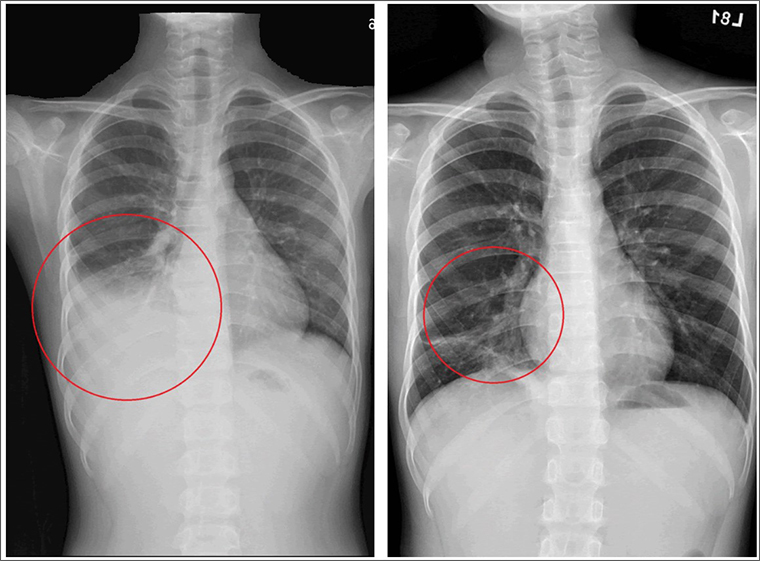

▲許小弟在一開始接受抗生素治療後仍然高燒未退,甚至出現肺炎擴散及肋膜積水的情形(左);先後使用口服四環黴素及喹諾酮類藥物進行治療後,肺部積水才明顯減少(右)。(圖/台北慈濟醫院提供)

不料病情瞬息萬變,在經抗生素治療後,許小弟仍然高燒未退甚至出現肺炎擴散及肋膜積水的情形,後來透過黴漿菌抗生素的調整,當晚許小弟即逐漸退燒,且在1週後平安出院,後續胸部X光追蹤亦發現右下肺炎及肋膜積水已改善。

以個案許小弟為例,在醫療團隊評估其症狀較為嚴重,且之前曾使用紅黴素治療,可能有紅黴素抗藥的情形,因此先後使用口服四環黴素及喹諾酮類藥物,發燒才逐漸改善,且在4天後肺部積水也明顯減少,病況穩定。吳秉昇提醒,醫師開立抗生素藥物會考量患者的年齡與臨床症狀嚴重度,並參考醫療指引進行治療,家長應遵從醫囑,按處方開立的劑量與時間讓孩童服用,且勿自行更改劑量與用藥時間。